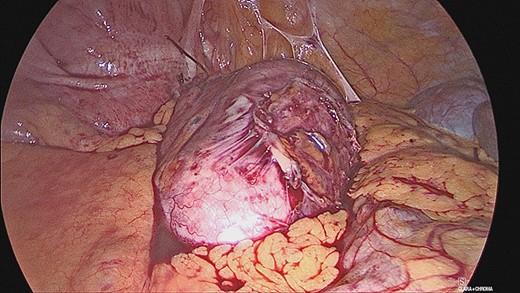

The appendiceal mucocele was visualised during the laparoscopic procedure. The adhesions surrounding the apex of the mucocele were released. There appeared to be volvulus of the appendix (Fig. 3). The main body of the appendix was normal with no evidence of malignancy seen during the surgery. On this basis, a right hemicolectomy was not performed. The appendix was amputated at the base and removed with the base tied (Fig. 4).

The patient was discharged from hospital the same day and followed up in clinic following histological analysis. Samples showed a grossly dilated appendix measuring 78 × 42 mm with a mesoappendix measuring up to 7 mm in thickness. Sections of the appendix revealed a thin wall with mucinous secretion in the lumen. There was complete replacement of epithelium lining by histiocytes with areas of multi-nucleated giant cell reaction. There was no evidence of any mucinous neoplasm.